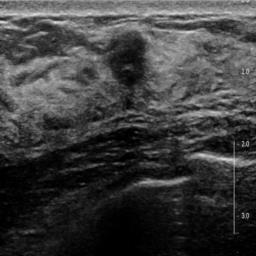

Ultrasonography is an important routine examination for breast cancer diagnosis, due to its non-invasive, radiation-free and low-cost properties. However, it is still not the first-line screening test for breast cancer due to its inherent limitations. It would be a tremendous success if we can precisely diagnose breast cancer by breast ultrasound images (BUS). Many learning-based computer-aided diagnostic methods have been proposed to achieve breast cancer diagnosis/lesion classification. However, most of them require a pre-define ROI and then classify the lesion inside the ROI. Conventional classification backbones, such as VGG16 and ResNet50, can achieve promising classification results with no ROI requirement. But these models lack interpretability, thus restricting their use in clinical practice. In this study, we propose a novel ROI-free model for breast cancer diagnosis in ultrasound images with interpretable feature representations. We leverage the anatomical prior knowledge that malignant and benign tumors have different spatial relationships between different tissue layers, and propose a HoVer-Transformer to formulate this prior knowledge. The proposed HoVer-Trans block extracts the inter- and intra-layer spatial information horizontally and vertically. We conduct and release an open dataset GDPH&GYFYY for breast cancer diagnosis in BUS. The proposed model is evaluated in three datasets by comparing with four CNN-based models and two vision transformer models via a five-fold cross validation. It achieves state-of-the-art classification performance with the best model interpretability.